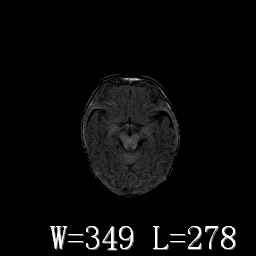

新生儿正常颅脑

hie?

脑干形态欠规则,信号增高,不知怎么解释?

脑干背侧面t1高信号是,新生儿正常已经髓鞘化好的部位